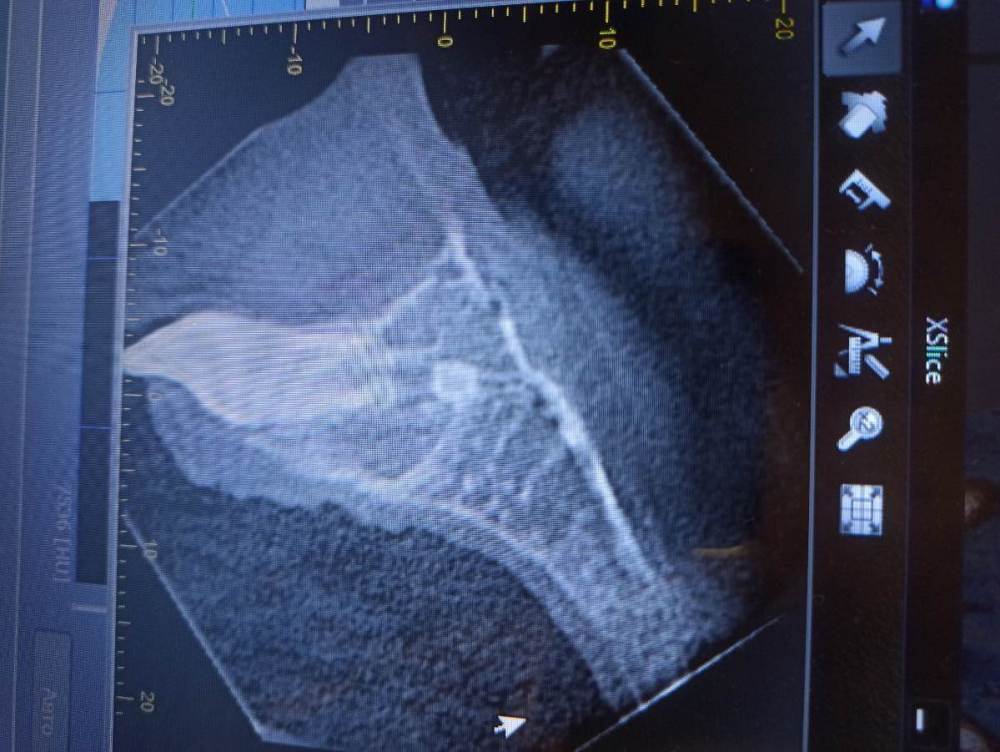

wladdX Опубликовано 4 июля, 2021 Поделиться Опубликовано 4 июля, 2021 Насколько могу судить по приложенным скринам, резорбция корня всё же есть. Судя по Вашему рассказу, проведённая коллегами работа была верной, результат весьма неплохой. Рассчитывать на длительное пребывание зуба 11 в челюсти не приходится. Когда-то его придётся удалить. 1 1 Ссылка на комментарий

wladdX Опубликовано 5 июля, 2021 Поделиться Опубликовано 5 июля, 2021 Резорбция корня + вертикальное расположение = анкилоз. То что зуб был с несформированной верхушкой корня помогло ему простоять так долго после реплантации в растущей челюстной кости. Конечно, хорошо бы, чтоб зуб смог простоять до имплантации, но на мой взгляд это маловероятно. 1 1 Ссылка на комментарий

Bier Опубликовано 6 июля, 2021 Поделиться Опубликовано 6 июля, 2021 Я вас не порадую: 1. Зуб анкилозирован. 3 часа в физрастворе = нет шансов на реваскуляризацию пульпы и связки. Судя по вашим снимкам однозначно анкилозирование. 2. Что делать теперь и почему: Зуб начал отставать в росте, еще через несколько лет это превратится в нерешаемую эстетическую проблему (вся челюсть будет расти, а зуб и участок челюсти с зубом - нет). Необходимо провести операцию декоронации (спилить коронковую часть зуба глубже уровня костной ткани, удалить то, что осталось от пульпы и дать так зажить. Остатки корня резорбируются сами с замещением на кость. Зато челюсть будет расти вместе с отстальными зубами. восстановить зуб временно на пластике (съемной) потом на брекетах. Имплантация желательно не раньше 21 года. Оставлять так нельзя! Ссылка на комментарий